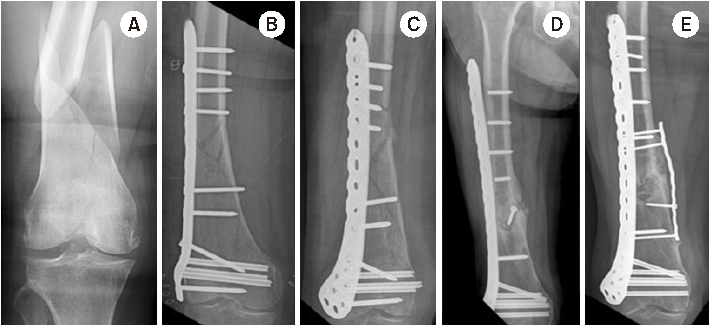

Fig. 6

(A) Radiograph of a distal femur fracture of a 74-year-old female after a ground-level fall. (B) Postoperative radiograph after a closed reduction and minimally invasive locked plating. (C) Six-week postoperative radiograph showing a stress riser fracture around the outermost locking screw after slip-down injury. (D) Radiograph showing bony union two years after overlapping intramedullary nailing. (E) Postoperative radiograph showing locked plating using a conventional cortical screw instead of a locking screw as a proximal outermost screw to minimize the stress riser.